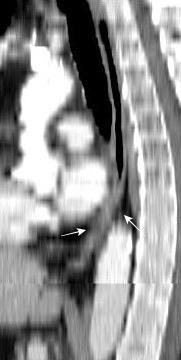

Traqueobroncomegalia de Mounier-Kuhn

Dilatación marcada de tráquea y grandes bronquios.

Traqueobroncomalacia 67% + Protrusión del tejido músculo-membranoso redundante entre los anillos cartilaginosos.(diverticulosis traqueal)

Infección respiratoria recurrente (88%)

Debilidad del aparato muco -ciliar Fumadores.